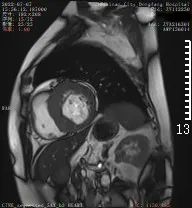

心脏磁共振检查

正式开展心脏磁共振(CMR)检查

是除心脏彩超、冠脉CTA之外的

另一种先进检查技术

具有无X线辐射、任意平面成像的优势

是集形态、灌注、功能及分子成像

于一体的成像技术

陈忠院长介绍

心脏磁共振能够对

心肌病、冠心病、先心病

心脏瓣膜病、心包疾病、心脏肿瘤

等病变进行诊断及鉴别诊断

在心脏形态与功能、心肌评估中

具有优势

对淀粉样心肌病、致密化不全心肌病等

具有独特诊断优势

半个月的时间,东方总院

已成功检查和诊断心脏病变3例